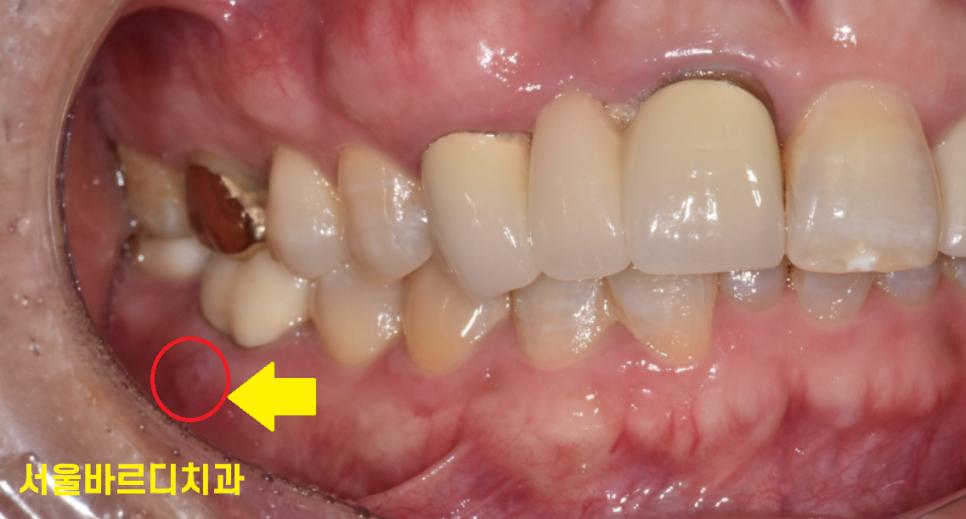

230516

잇몸 물집이라 표현하신 부분이에요~

하얗게 보이기도 하여

헐어보이기도 하지만

2번 이상 같은 증상이 반복되셨다면

강일역 치과를 내원하셔야해요.

원인이 해결되지 않으니까 재발되는 것인데

주변 치아들도 위험하게 만드는

시한폭탄같은 존재거든요ㅠㅠ